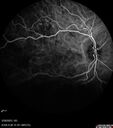

West Nile Virus Multifocal Choroiditis with later CNVM70 x angesehen77 year old female with vision loss in the left eye treated with Anti-VEGF